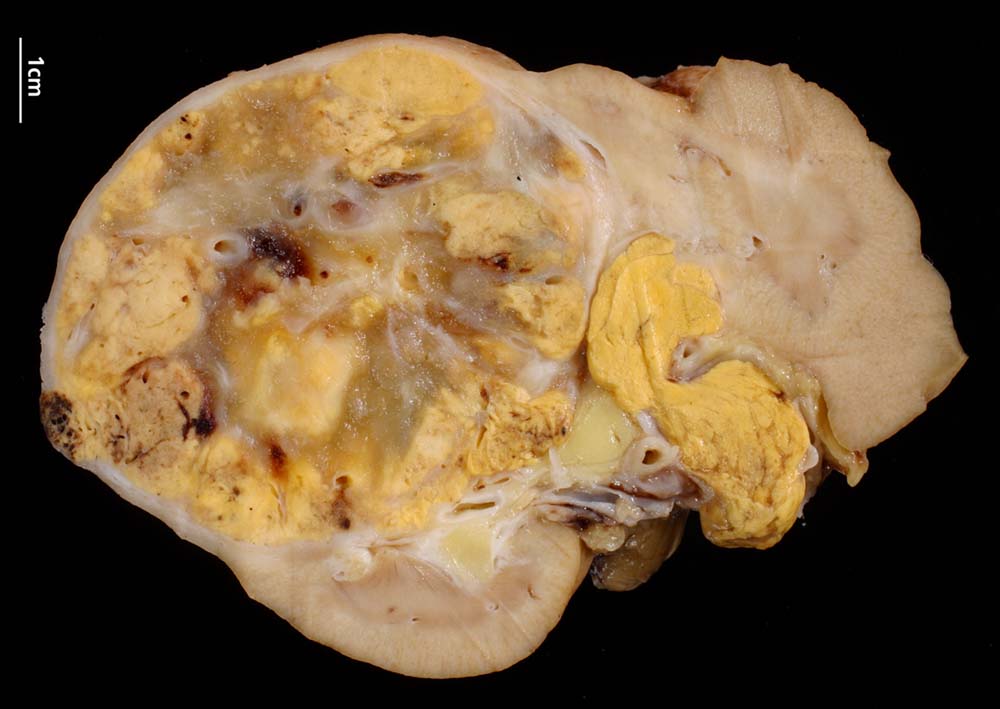

Die Schnittfläche der meist solitären klarzelligen Karzinome ist hellgelb bis grauweiss, oftmals mit Nekrosen, Blutungen und Zystenbildung. Dadurch entsteht das charakteristische „bunte“ Bild dieser Tumoren. Nierenkarzinome bilden zum angrenzenden Parenchym teilweise eine Pseudokapsel. Grosse Tumoren können in das perirenale Fettgewebe, das Nierenbecken oder nicht selten die Nierenvene einbrechen. In Einzelfällen entstehen Tumorthromben in der Vena cava, die bis in den rechten Herzvorhof reichen können. Wegen der Ähnlichkeit der Tumorzellen mit den Zellen der Nebennierenrinde wurden klarzellige Nierenzellkarzinome früher als „Hypernephrom“ bezeichnet.

• Saum von komprimiertem und fibrosiertem Nierenparenchym unmittelbar angrenzend an das Karzinom (makroskopisch als Pseudokapsel imponierend). Übriges nicht-neoplastisches Restnierenparenchym mit leichter tubulointerstitieller Fibrose und Atrophie.

• Expansiv wachsender, scharf begrenzter knotiger Tumor ohne Durchbruch der Nierenkapsel.

• Wenig zellarmes Tumorstroma mit Blutungsresiduen.

• Solide Tumorzellaggregate eingefasst von dünnen Bindegewebssepten mit zahlreichen dünnwandigen Blutgefässen.

• Frische intratumorale Einblutungen und Blutungsresiduen (Siderinpigment)